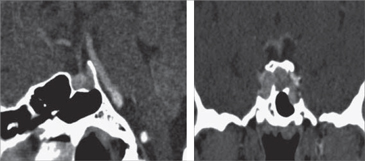

También se constató activación de su Acromegalia con niveles de GH de 12,7 ng/ mL, con Glicemias de 89,3 mg/dL basal, 190,8 mg/dL a los 30 minutos, 214,5 mg/dL a los 60, 199,3 mg/dL a los 90 y 123,2 mg/dL a los 120 minutos; con un IGF-1 de 674 ng/mL (Valor normal para edad: 87-238 ng/ mL). No se pudo realizar una Resonancia Nuclear Magnética por el Gadolinio; por lo cual luego de ingresar a hemodiálisis se realizó un TC de silla turca (Figura 1). En ésta, se apreció sólo cambios post quirúrgicos en el piso selar y un material con densidad de partes blandas ocupando la logia selar, de diámetro cráneo-caudal de no más de 6 mm.

Figura 1. TAC de silla turca pre tratamiento.